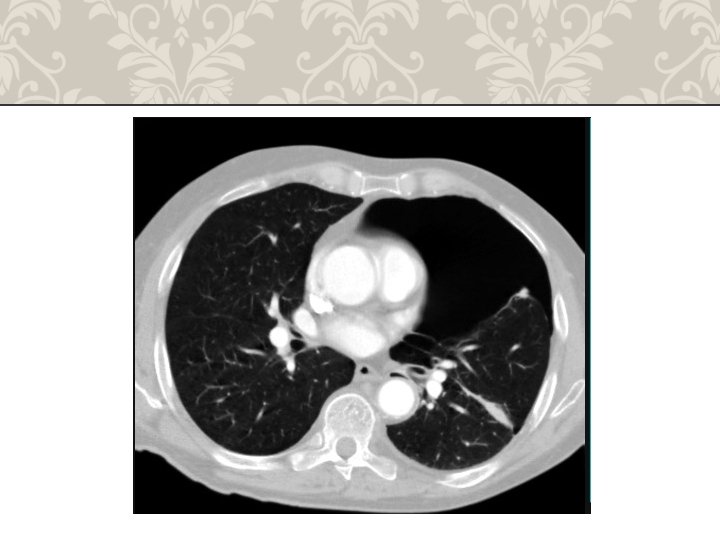

HEMOTHORAX life-threatening injury number one A massive hemothorax is defined as >1500 m. L of blood or, in the pediatric population, one third of the patient's blood volume in the pleural space tube thoracostomy is the only reliable means to quantify the amount of hemothorax After blunt trauma, a hemothorax usually is due to multiple rib fractures occasionally bleeding is from lacerated lung parenchyma a massive hemothorax is an indication for operative intervention Indication of emergency toracotomy

HEMOTHORAX

RIB FRACTURE WITH HEMOTHORAX